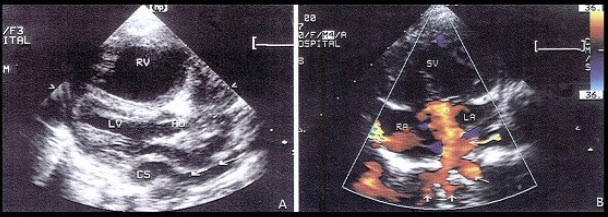

4、单项选择题

图为小儿超声心动图,根据此切面可以看到哪些腔室结构()

A.左房、左室、主动脉、右室、右房

B.左房、左室、主动脉、右室、右室流出道

C.左房、左室、主动脉、右室

D.左房、左室、右室、右房

E.左房、左室、主动脉、左心耳、右室、右房、右室流出道

10、单项选择题

20、单项选择题 超声诊断脑积水(中期)的指征是()

如图,二维超声心动图中,此为____________切面。